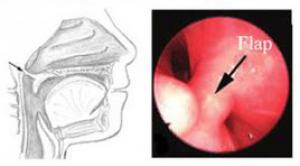

Pharyngeal flap

In a pharyngeal flap, tissue from the back of the throat is elevated and then connected to the back of the palate. The pharyngeal flap partially obstructs the space between the palate and throat. The partial obstruction significantly reduces the amount of air flow through the nose during speech